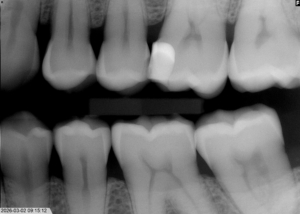

Intraoral röntgen

Vanligaste förekommande röntgenundersökningen i Sverige. Den används vanligen för att upptäcka tidig karies, tecken på tandlossningssjukdomar, tandsten och andra sjukdomar i munhålan. Röntgenstrålning som passerar genom tänderna fångas upp av en digital sensor som placeras i munnen. Du får en halskrage under hakan som skydd mot röntgenstrålningen.